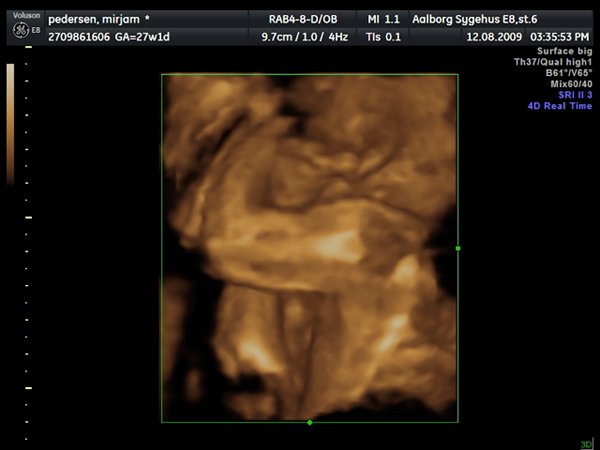

Så var jeg til 3D scanning, og det er en lille PRINSESSE

Hun var bestemt ikke samarbejds villig, vi skulle ihvertfald ikke bestemme hvordan hun sku ligge, så hun lå med hænderne oppe foran hovedet og somme tider med benene oppe foran os.. Så jeg fik rabat kom af med 800kr og han scannede mig ca 50 min. Han sagde hun vejede 990 gram

ups fik ikke billeder tilføjet

Vedhæftede fotos (klik for at se i fuld størrelse)